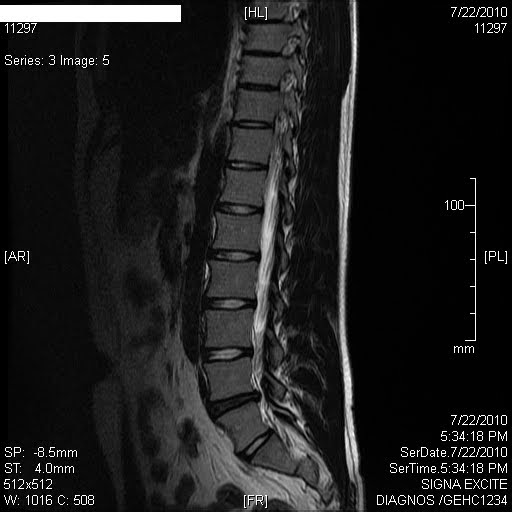

Magnetic Resonance Imaging or Mri Scan Report of Spinal Cord or Lumbar …

Sagittal MRI of herniated L5-S1 lumbar disc. #LowerBackPain | Bulging …

MRI of a Lumbar-Disk Herniation – License, download or print for £9.92 …

Herniated Disc Mri L5 S1 – Lumbar Herniated Disc – A More in Depth Look …

Pre-operative lumbar MRI showing a right paracentral disc herniation at …

Medical Endeavors w/ my Herniated and Degenerative Lumbar Disc: MRI …